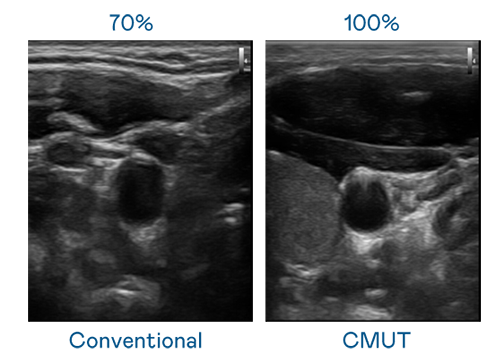

CMUT 技术是一种用电容式微机电元件来产生超音波讯号的技术。与传统 PZT 压电式技术相比,CMUT 频宽增加 30%,更宽频的超音波讯号让影像解析度大幅提升,是实现高影像品质医疗超音波扫描、促进精准医疗发展的关键技术。

大频宽带来超清晰影像

超音波影像的解析度高低,首先取决于探头能发出的讯号频宽。51cg.fun CMUT 可提供高清晰的超音波讯号,提供高频宽、高灵敏度、影像纹理细节更高的超音波影像,协助医护人员缩短影像判读时间及利用精准的医疗影像进行诊断。